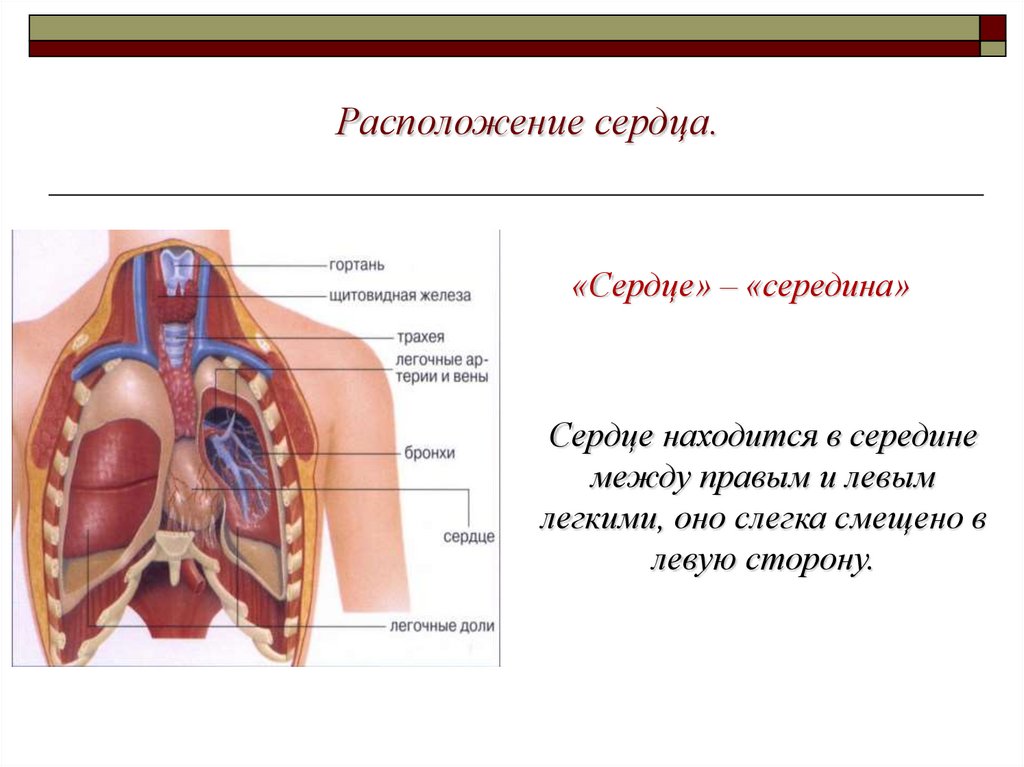

Где находится сердце у человека.

Сердце у человека располагается.

Сердце у человека располагается в грудной полости.

Расположение сердца у человека.

Анатомическое расположение сердца.

Сердце в грудной клетке расположено.

Где расположено сердце у человека анатомия.